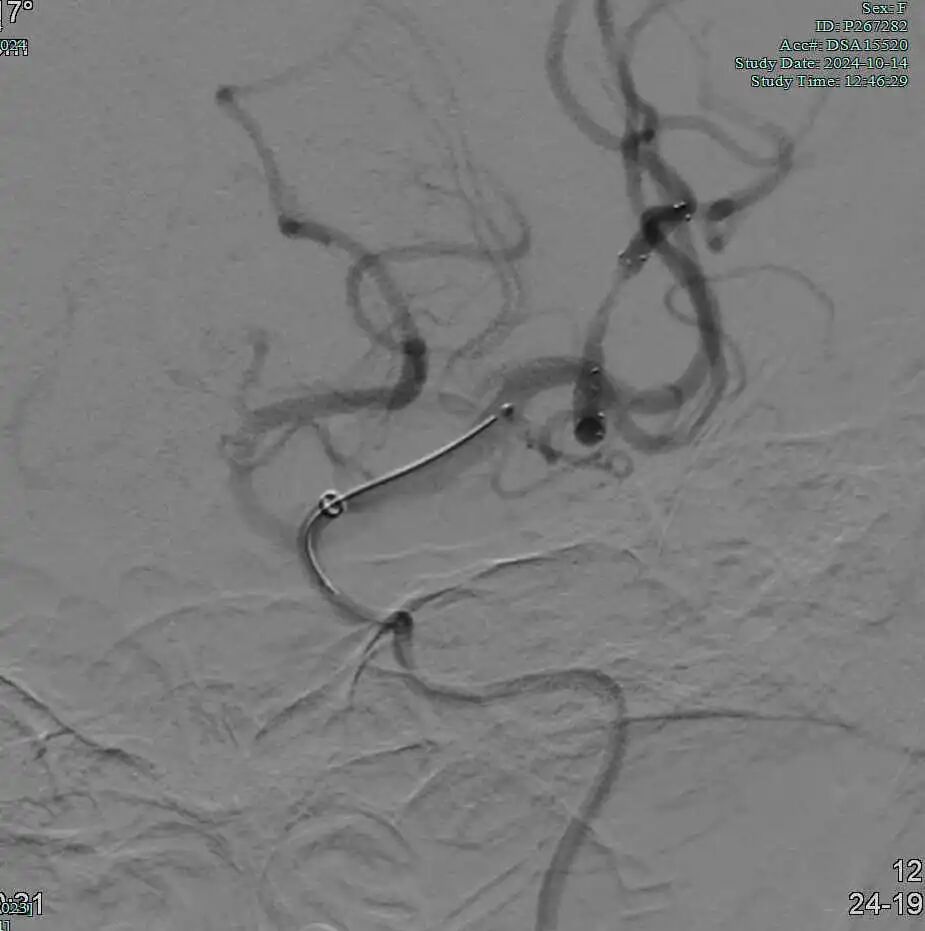

Tarvos微导丝携微导管超选大脑中下干M2末端。

动脉长鞘怎么置入有励可说|Locaste 088励楷长鞘及Tarvos微导丝在左侧大脑中动脉闭塞取栓术中的应用_https://www.jmylbn.com_新闻资讯_第11张

动脉长鞘怎么置入有励可说|Locaste 088励楷长鞘及Tarvos微导丝在左侧大脑中动脉闭塞取栓术中的应用_https://www.jmylbn.com_新闻资讯_第12张

取栓后下干再通,上干仍闭塞。